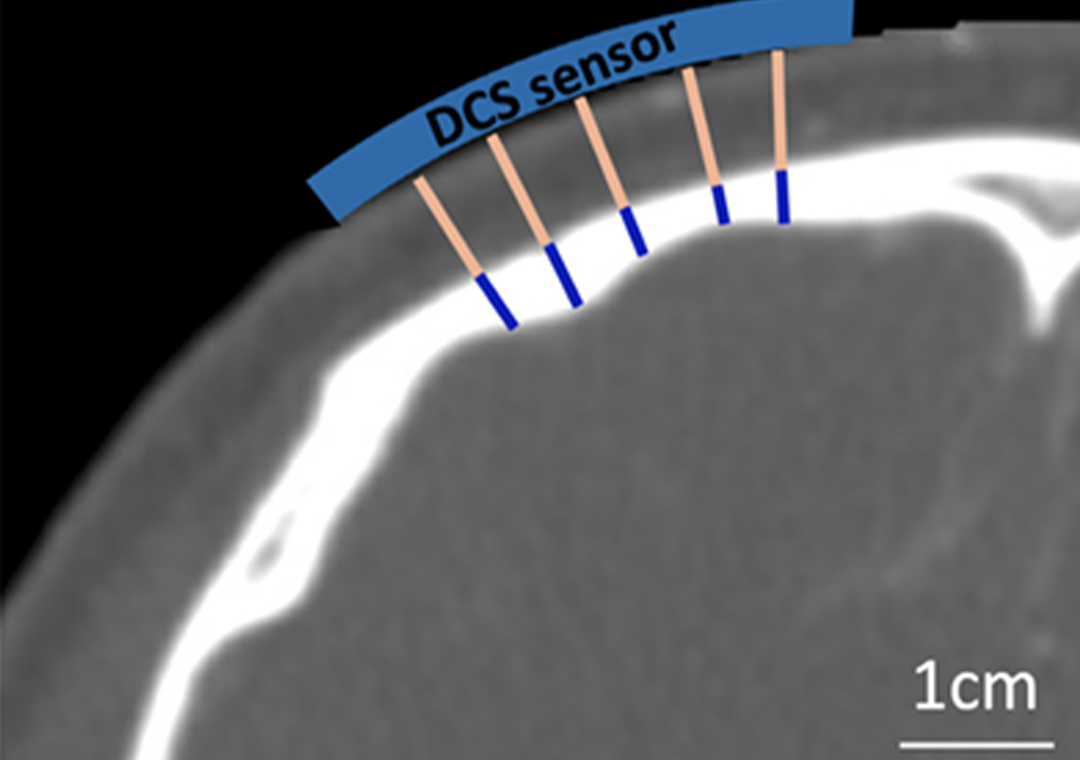

Comparison of diffuse correlation spectroscopy analytical models for measuring cerebral blood flow in adults

Download Document Comparison of diffuse correlation spectroscopy analytical models for measuring cerebral blood flow in adults…